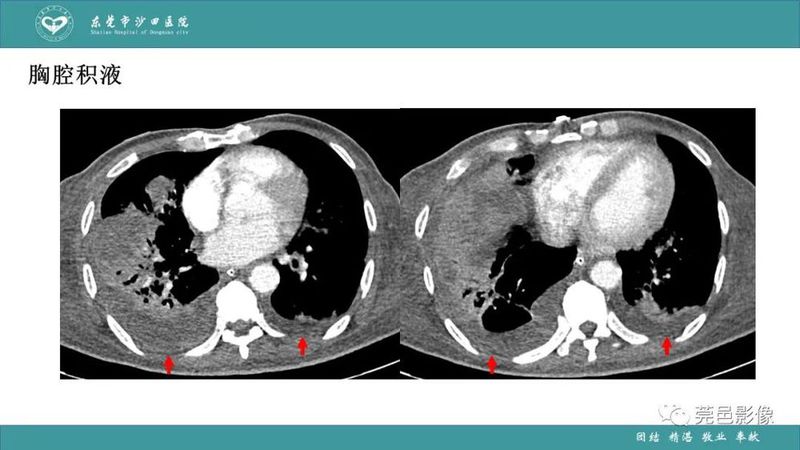

「肺炎克雷伯杆菌肺炎」影像学诊断+鉴别诊断